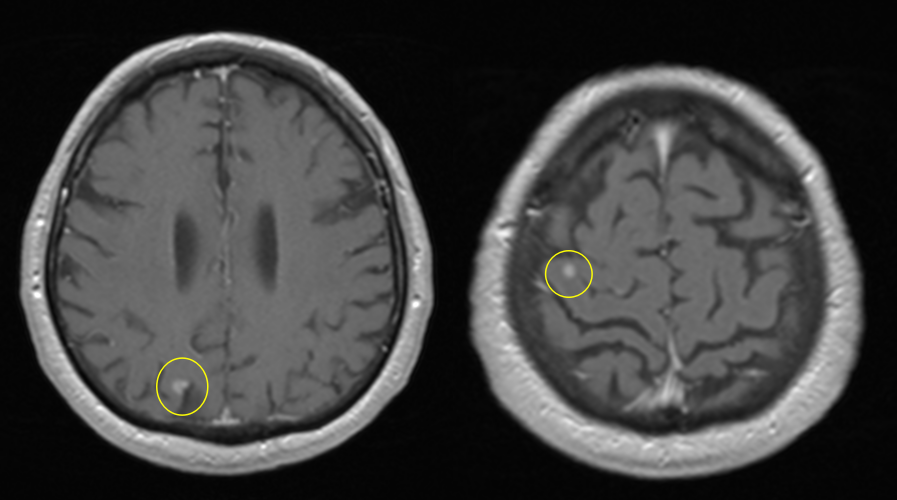

- Imagistică cerebrală: RMN-ul cu substanță de contrast este metoda de elecție, dar și CT-ul poate fi util.

- Radiochirurgia stereotactică (Gamma Knife, CyberKnife) – recomandată pentru metastaze unice sau puține, bine localizate, cu dimensiuni sub 2 cm.

Se face cu tumori cerebrale primare (glioblastom, astrocitom, etc.), abces cerebral, leucoencefalopatie multifocală progresivă, scleroză multiplă sau accident vascular cerebral.

Metastazele cerebrale apar frecvent în emisferele cerebrale (80%), mai rar la nivelul cerebelului (15%) sau trunchiului cerebral (5%). Localizarea influențează simptomele și posibilitățile de tratament.